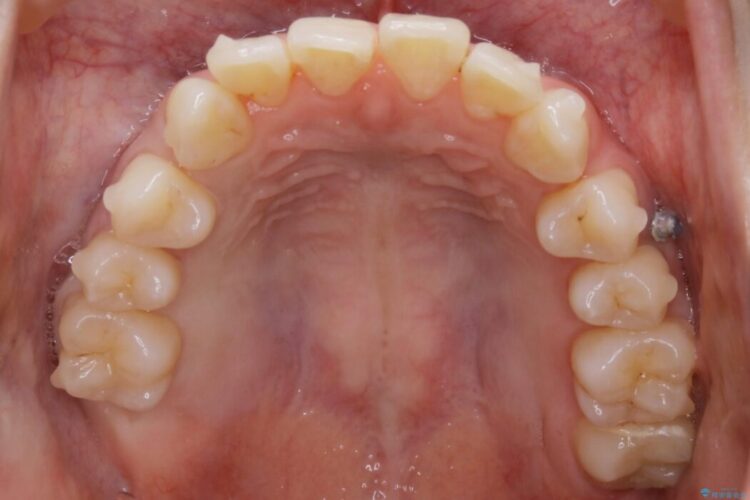

【20代女性】ブライダルに向けた矯正できれいなスマイルラインへ

- 患者様:20代女性

- 治療期間:1年10ヶ月

- 矯正装置:インビザライン コンプリヘンシブパッケージ

笑った時に見える歯並びをきれいにしたいとの主訴で来院されました。

ガタつきの度合いから抜歯は不要と判断しましたので、マイクロインプラントを用いて歯全体を遠心移動させていくことでねじれや噛み合わせのズレを改善していく計画を立てました。